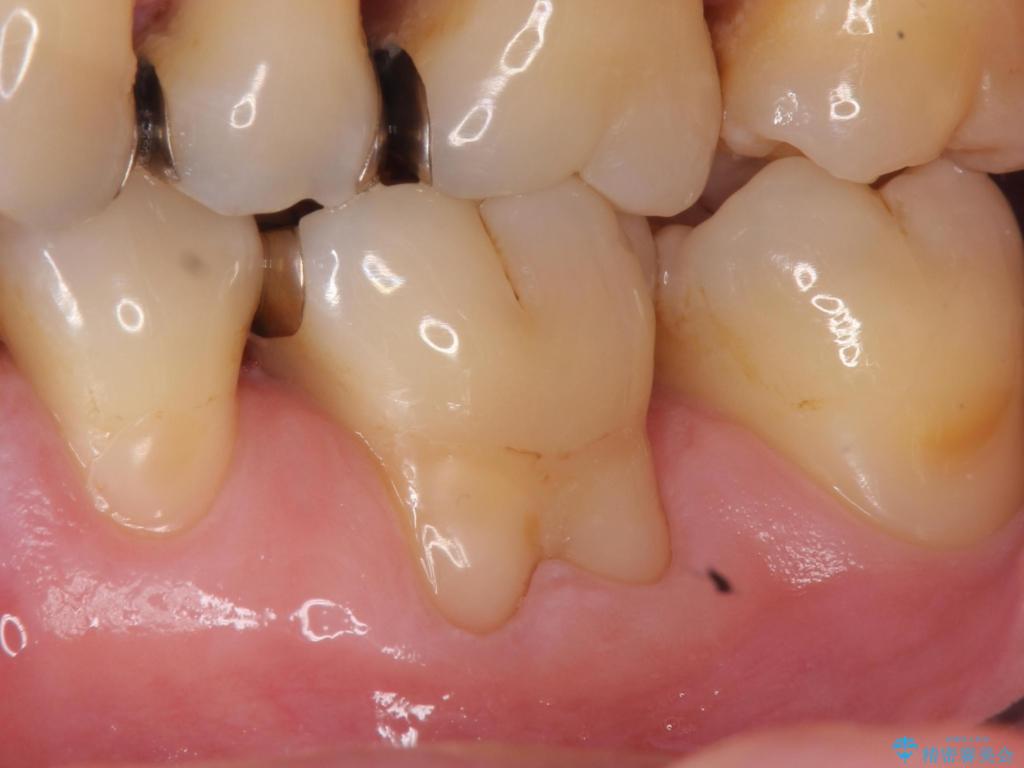

歯根の分岐部よりも根尖側の頬側面が露出している状態でしたが、露出部位を分岐部までに抑えることができました。

しみる症状も改善され、大変喜んでいただけました。

術後は歯肉が下がらないよう経過を追っていきます。